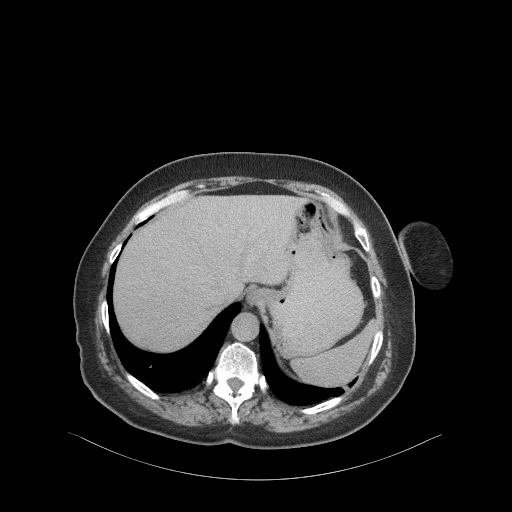

Original VENOUS CT scan

Full window (WL 1023.5, WW 4095 β†’ Low βˆ’1024, High +3071)

Lung window (WL -600, WW 1500 β†’ Low βˆ’1350, High +150)

Mediastinum window (WL 40, WW 400 β†’ Low βˆ’160, High +240)